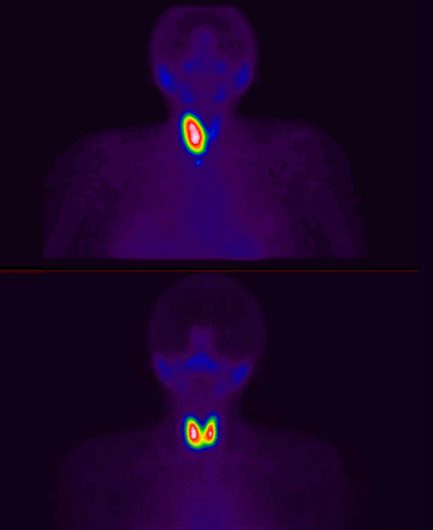

131I-Yodo radiactivo

- Hipertiroidismo

- Cáncer de Tiroides

Gammagrafía

- Tiroides

- 131I-Yodo radiactivo

Yodo radiactivo

Yodo radiactivo (Yodo131; I-131; 131I)

Hipertiroidismo

Cáncer de tiroides